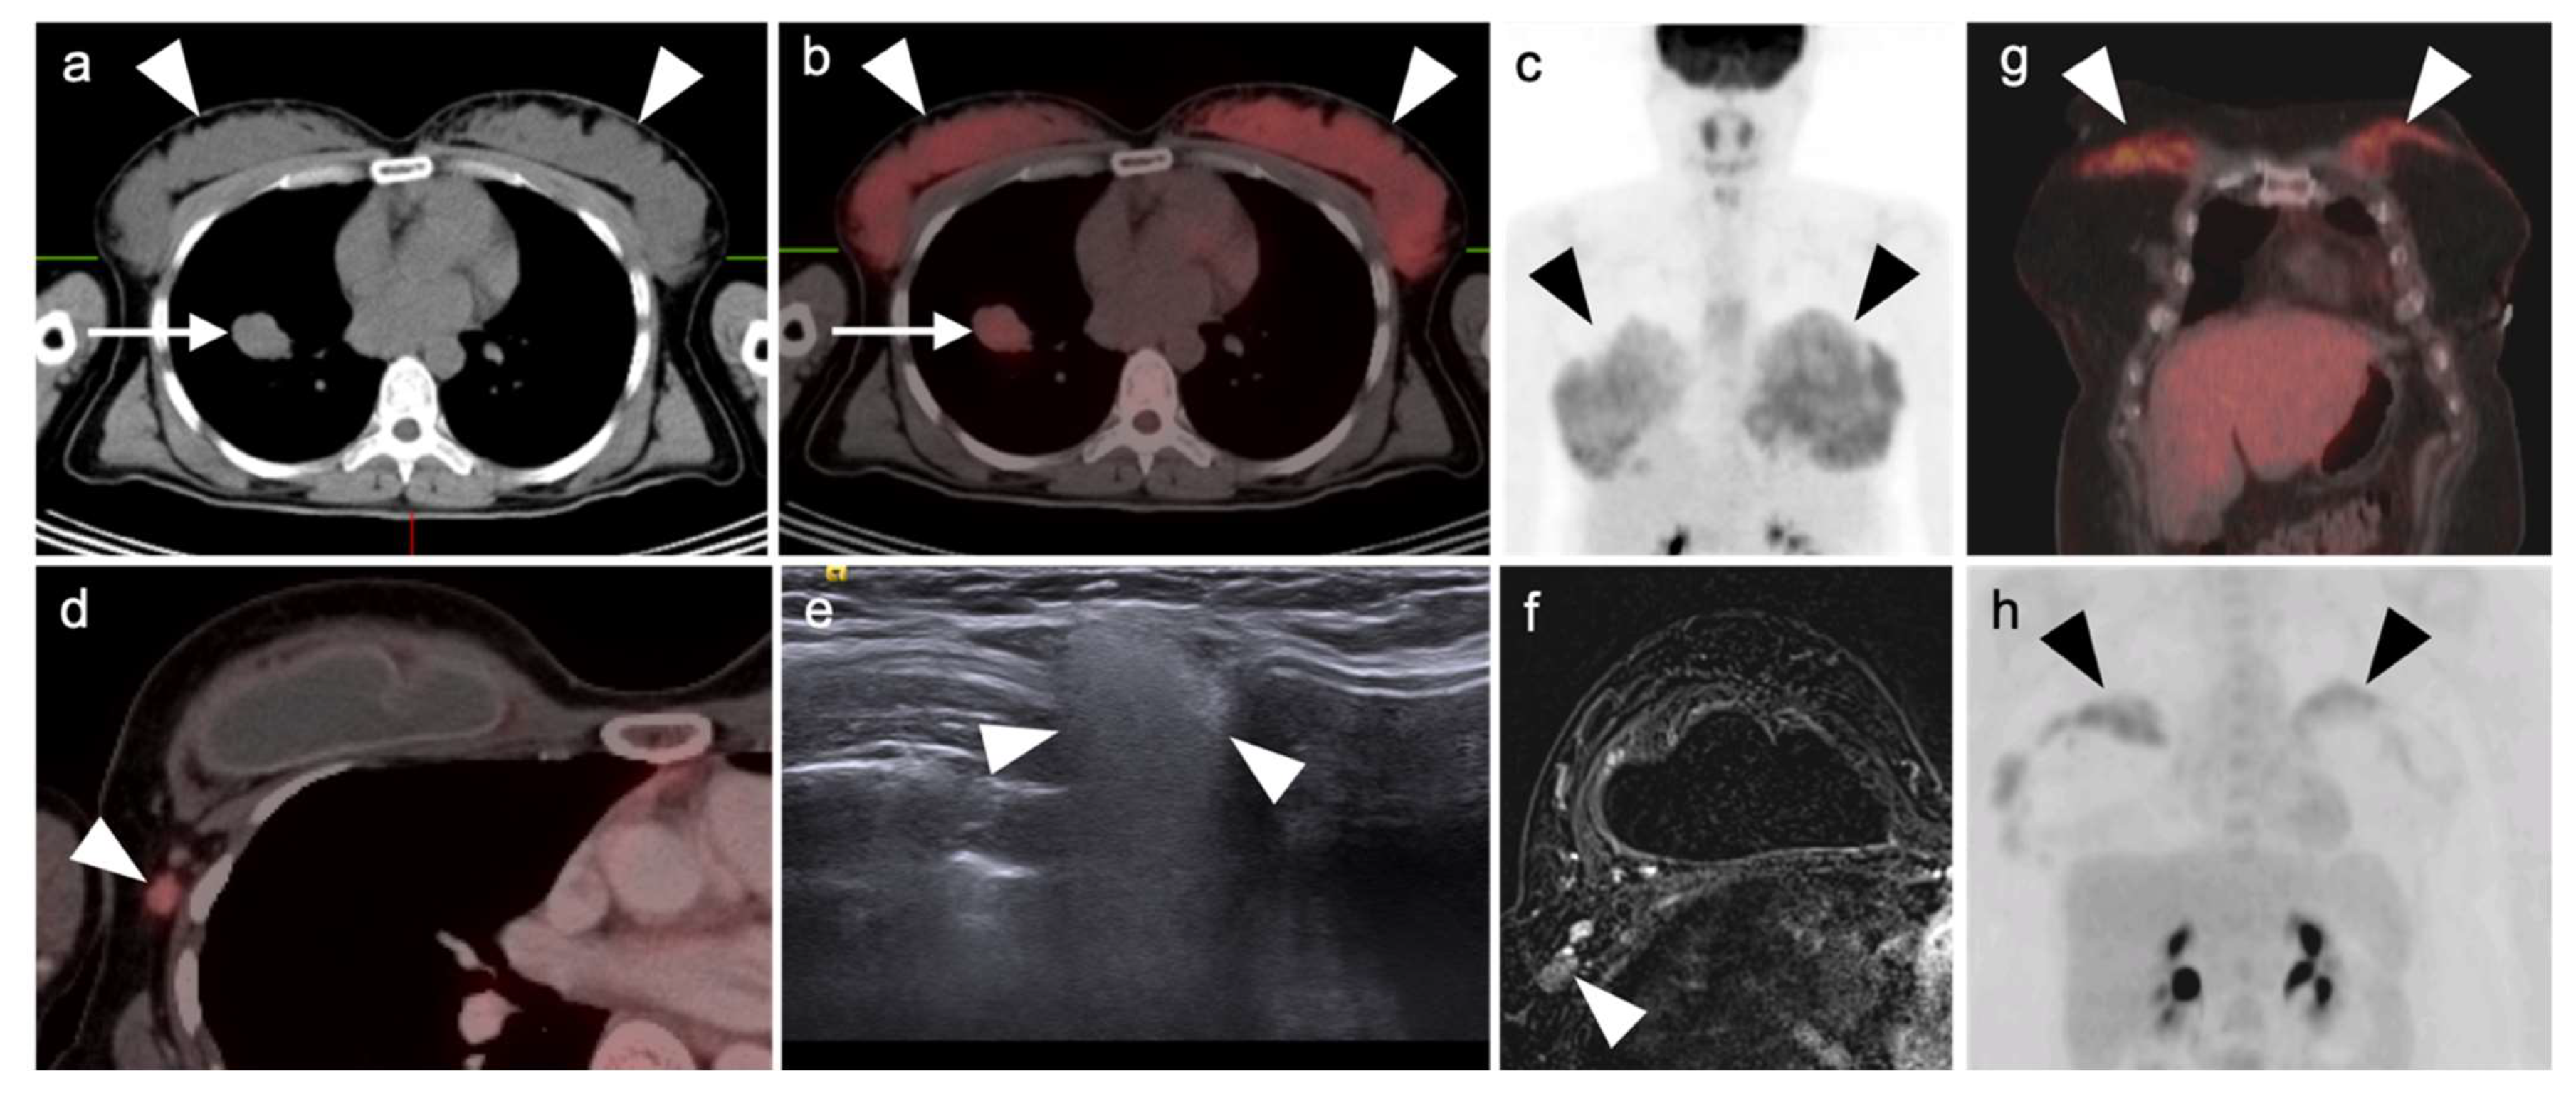

In diagnostic imaging of MPM, FDG PET-CT, whole-body MRI and PET-MRI show superiority over conventional CT [51]. MPM is typically intensely hypermetabolic on FDG PET-CT, making it highly amendable to staging by this method (Figure 13 and Figure 14). Hypermetabolic pleural thickening is typically associated with calcified pleural plaques but can be mimicked by hypermetabolic host inflammatory reaction to talc pleurodesis, empyema, and other pleural inflammatory disease, or by other subpleural malignant processes (Figure 15) [52]. NCCN endorses the use of FDG PET-CT to stage patients only if they are being considered for surgery [53]. However, FDG PET-CT may under-stage mediastinal or nodal disease in MPM and is typically best used for assessment of distant metastases [54]. PET-CT should be done prior to contemplated talc pleurodesis. NCCN also supports the use of FDG PET-CT for mediastinal assessment based on possible evidence of disease progression following induction chemotherapy.

In summary, MPM is typically intensely hypermetabolic on FDG PET-CT, but can be mimicked by hypermetabolic host inflammatory reaction to talc pleurodesis, or other inflammatory or malignant pleural processes. The best use of FDG PET-CT for staging should be reserved for patients considered for surgery or for assessment of suspected disease progression despite induction chemotherapy, with the realization that FDG PET-CT may under-stage mediastinal or nodal disease.